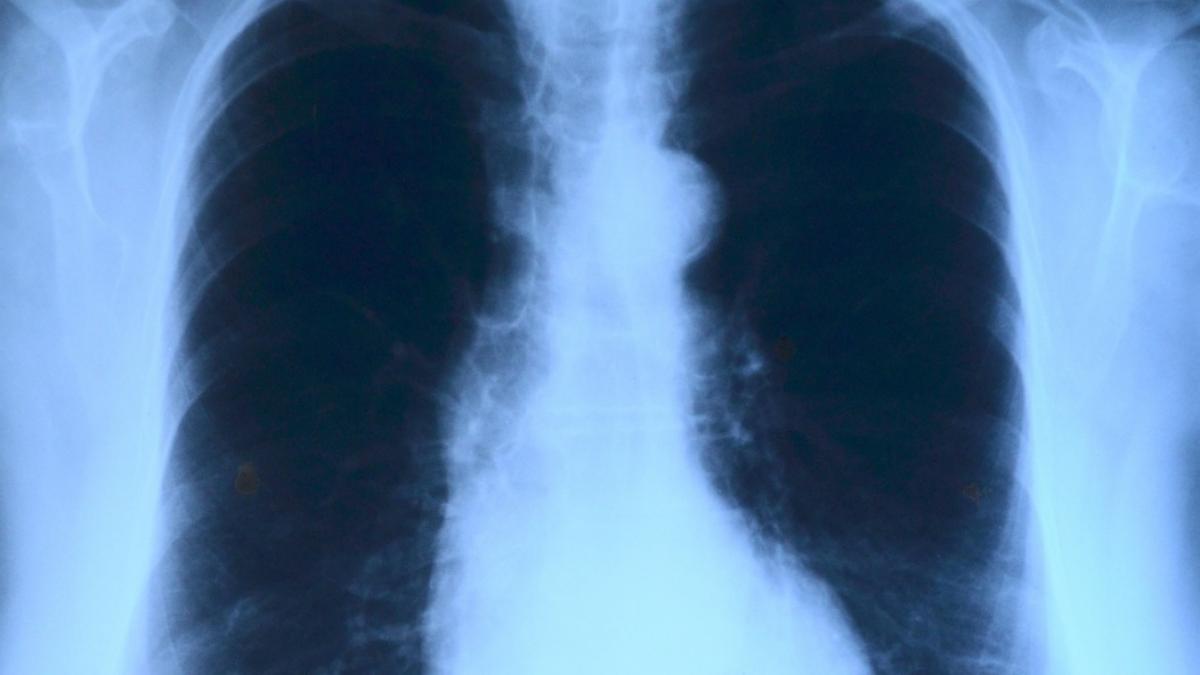

E uluitor cât de repede pătrunde noul coronavirus în plămânii unui bărbat de 50 de ani. Medic: „Puteți vedea distrugerea”27 Mar